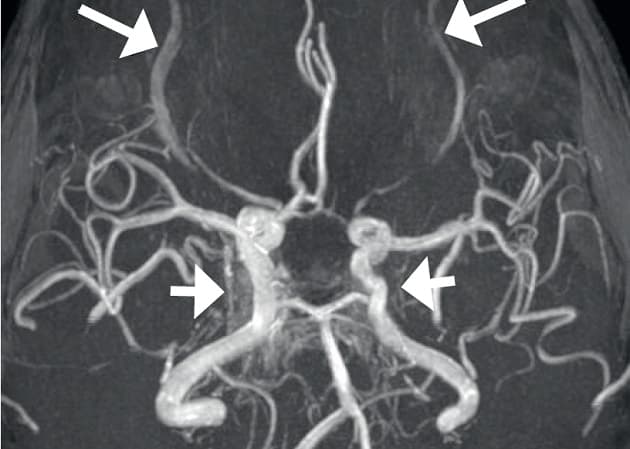

© Tredimensionel time of flight-MR-angiografi med maksimum intensity projection.

En midaldrende kvinde med to tidligere lette hovedtraumer blev akut indlagt med dobbeltsyn, hovedpine, kvalme og svimmelhed. Efter normalt resultat af CT af cerebrum påbegyndtes behandling med trombocythæmmere på mistanke om hjernestammeinfarkt. MR-angiografi viste dog en anden årsag til symptomerne. Læs mere om diagnosen og behandlingen i kasuistikken af Hansen et al.

Sjælden dural sinus cavernosus-fistel var årsag til okulomotoriusparese